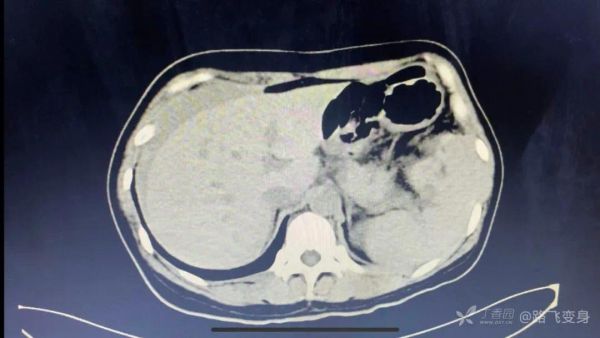

病人出现「休克」症状,没有办法只有准备手术,术前常规行全腹部 CT 检查,如下:

CT 发现明显异常。可以和下面第一次急诊 CT 视频做对比。

丁香园站友 @旧故里草木生 认为:两张片子对比,最明显的改变是脾脏周围有异常混杂密度影,肝周积液,又是个育龄期女性,大胆猜测脾脏异位妊娠导致的破裂。

丁香园站友 @zhangzihua87 认为:腹腔出血伴休克是没有疑问的。第一次 CT 脾门附近可疑软组织密度,第二次 CT 肝周积液,脾门软组织密度增大、不均,考虑破裂。一般考虑脾门血管瘤破裂。与妇科手术有关的话,大胆推测子宫内膜异位破裂。